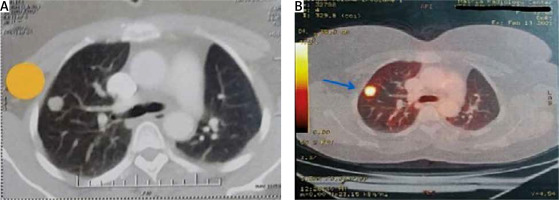

All eligible patients were discussed in multidisciplinary team (MDT) meetings including a surgeon, medical oncologist, radio-oncologist, radiologist and pathologist to estimate the potential benefit of surgical resection. For all patients, full medical history (including primary site type and previous chemo/radiation therapy received) was sought. Thorough clinical examination, routine laboratory investigations and lung function tests were performed. Single breath thin-slice IV contrast chest CT was performed within 4 weeks of the surgery to plan the type of procedure (Figure 1 A). Staging for extra-thoracic disease was performed depending on the primary tumor. Fluorodeoxyglucose positron emission tomography (FDG-PET) was proposed in most cases to exclude extra-thoracic metastases, determine the metabolic activity of lung nodules and assess the nodal disease (Figure 1 B). In selected cases, a brain magnetic resonance imaging (MRI) study was also done to exclude central nervous system (CNS) metastasis.

Figure 1

Preoperative imaging studies: showing right upper lobe solitary lung nodule in chest CT (A) (yellow tag) and PET-CT (B) (blue arrow) for 48-year-old female patient with history of urinary bladder urothelial carcinoma operated by VATS wedge resection